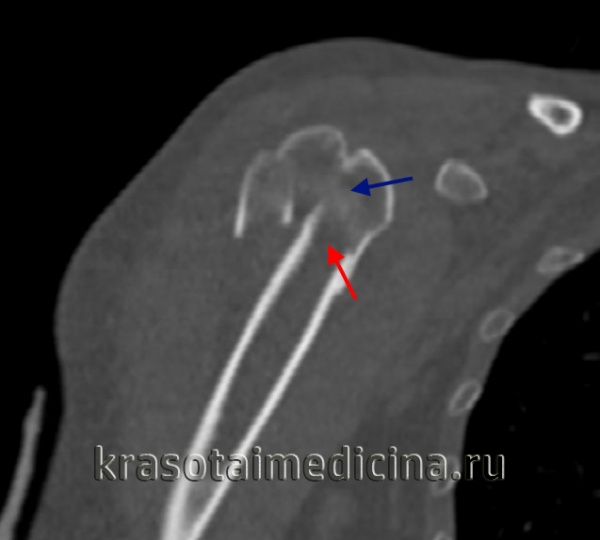

КТ плечевого сустава. Оскольчатый перелом хирургической шейки плечевой кости со смещением отломков. Дистальный отломок (красная стрелка) вколочен в проксимальный отломок (синяя стрелка).

Проксимальные переломы

Возможен перелом головки, отрыв малого или большого бугра, перелом анатомической и хирургической шейки плеча. Наиболее распространены переломы хирургической шейки, причем подавляющую часть пострадавших составляют люди пожилого возраста. Причиной перелома обычно становится падение на локоть, плечо или отведенную руку.